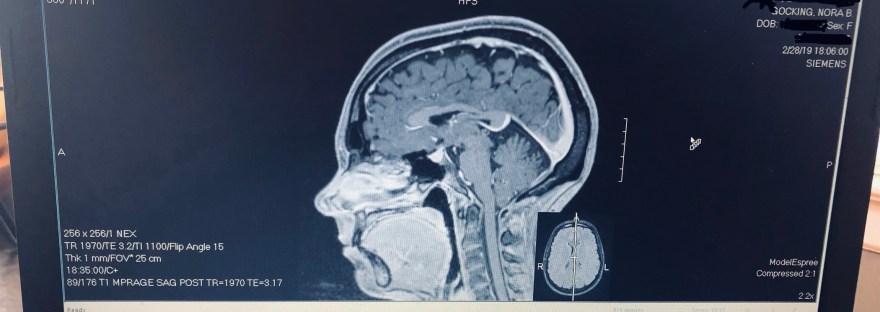

MRI Madness

For many, March is all about March Madness... basketball, tournaments, spring, fun! For me, it's quite a bit different. March is all about MRI Madness in our house. Time for the pre-authorizations, phone calls from insurance companies verifying my very expensive scan, expensive copay's, messaging my favorite MRI tech to make sure she's working during… Continue reading MRI Madness